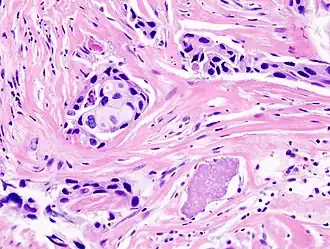

Colorées par l'hématoxyline et l'éosine, des cellules d'un carcinome du sein.

L'anatomopathologie, anatomo-pathologie ou anatomie pathologique[1], informellement abrégée en « anat-patho » ou « anapath » dans le jargon des professionnels de la santé, est une spécialité médicale humaine et vétérinaire. C'est la partie de la pathologie consacrée à l'étude morphologique des anomalies macroscopiques et microscopiques des tissus biologiques et des cellules pathologiques prélevés sur un être vivant ou mort.

L'anatomopathologie étudie les lésions macroscopiques et microscopiques de tissus prélevés sur des êtres vivants malades ou décédés par biopsie, frottis ou biopsie extemporanée. Selon qu'elle s'intéresse à l'Homme ou à l'animal, on distingue l'anatomopathologie humaine et l'anatomopathologie vétérinaire.

L'anatomie pathologique, parfois appelée « pathologie » de manière abusive (cf. « pathology » des anglo-saxons), est une spécialité médicale méconnue du public et pourtant primordiale en cancérologie. Elle a pour objectif d’analyser principalement au microscope les prélèvements tissulaires et tumoraux réalisés chez les patients et d’en déduire le diagnostic et les principaux facteurs de gravité de la tumeur, contribuant ainsi pour la plus grande part à la décision thérapeutique.

Ces examens sont effectués sur tout prélèvement tumoral et constituent la base du diagnostic de cancer. Ils sont souvent complétés par une analyse immunohistochimique qui a pour objectif d’identifier des protéines fabriquées par les cellules tumorales — ce qui permet souvent de mieux classer la tumeur, d’en évaluer la gravité et de prédire l’efficacité de certains médicaments — et de plus en plus, par des analyses moléculaires de l’ADN et des ARN des cellules tumorales.

Tous les prélèvements confiés en pathologie sont préservés dans des petits blocs de paraffine. Une tranche fine de quelques microns d’épaisseur (rubans) est réalisée sur tous les blocs, déposée sur une lame de verre et colorée pour être examiné au microscope. Les lames, blocs de paraffine et images peuvent facilement être échangés entre médecins pour une nouvelle interprétation si le patient est traité par une autre équipe médicale, ou pour un second avis auprès d’un collègue référent pour un type de tumeurs particulier en cas de difficulté diagnostique.